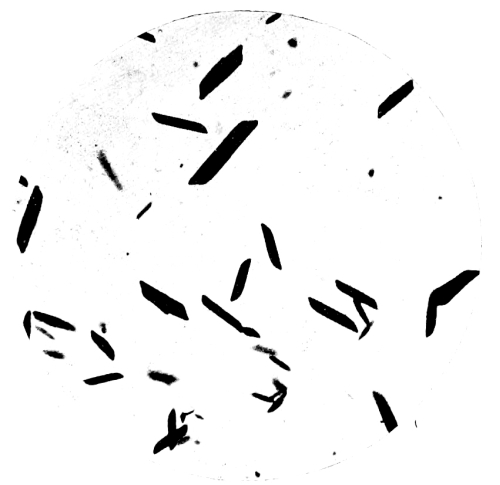

30. Photo-micrograph of Sublimate of Arsenious Acid obtained by Reinsch‘s Process 284